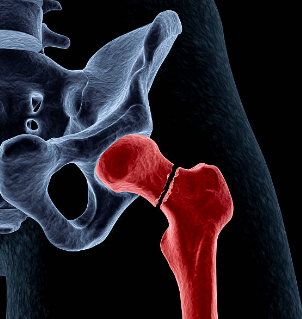

고관절 골절이란?

골다공증과 같은 뼈 약화 상태 또는 외상으로 인해 발생하는 대퇴골(허벅다리 뼈) 상단의 골절을 의미하는 것입니다. 일반적으로 낙상이나 직접적인 충격으로 인해 발생하며, 특히 고령자에서 흔히 일어날 수 있는 사고입니다. 고관절 골절치료는 주로 수술과 재활이 필요하며, 이는 환자의 이동과 삶의 질에 많은 영향을 미칠 수 있습니다.